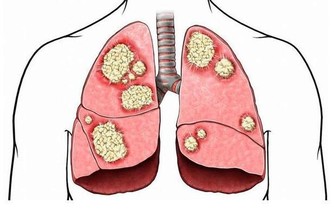

食鹽過多不僅會引發高血壓、氣管炎,還可增加胃癌的發病風險。高鹽膳食使胃酸減少,抑制前列腺素E2,使胃黏膜易受損,發生胃炎或胃潰瘍,繼而引發胃癌。喜食醃製食品也是誘發胃癌的一大因素。因為醃製的菜會產生亞硝酸鹽,亞硝酸鹽在胃中與胺類物質結合形成的亞硝胺可引發胃癌。